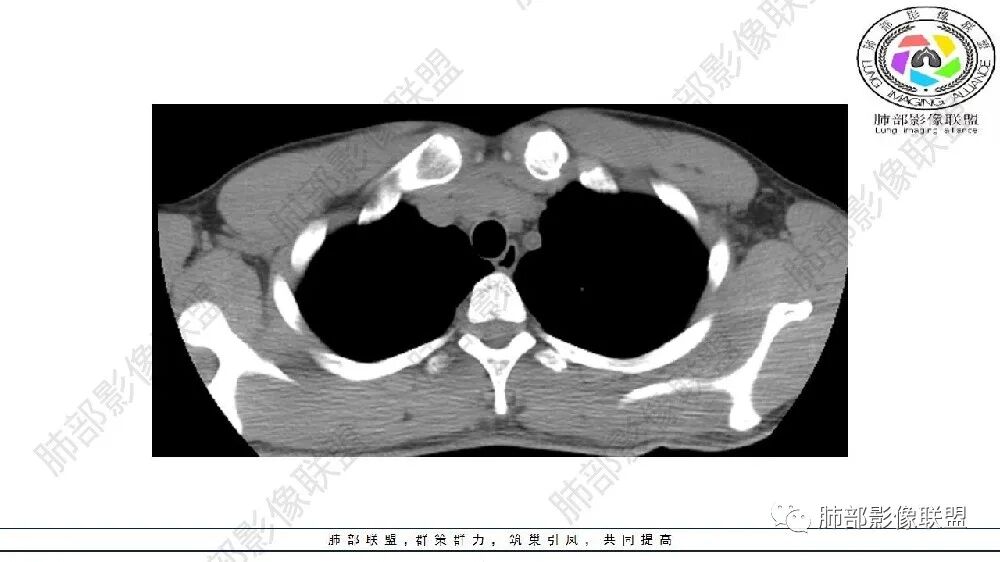

左肺下叶多发大小不等囊腔伴周围磨玻璃影,可见血管增粗,似与胸主动脉相连,考虑肺隔离症,鉴别CPAM。

左肺下叶多发囊腔、结节,及磨玻璃密度影,考虑肺隔离症,鉴别CCAM

左肺下叶多发囊腔、斑片、索条(粗大扭曲的血管?)降主动脉左侧有血管影?首先考虑肺隔离症,建议增强扫描,鉴别囊腺瘤样畸形

左肺下叶多发囊腔,粗大血管影,隔离征可能,鉴别气道畸形。

青年男性,左肺下叶多发囊腔伴磨玻璃影,并见增粗血管影,考虑肺隔离症。